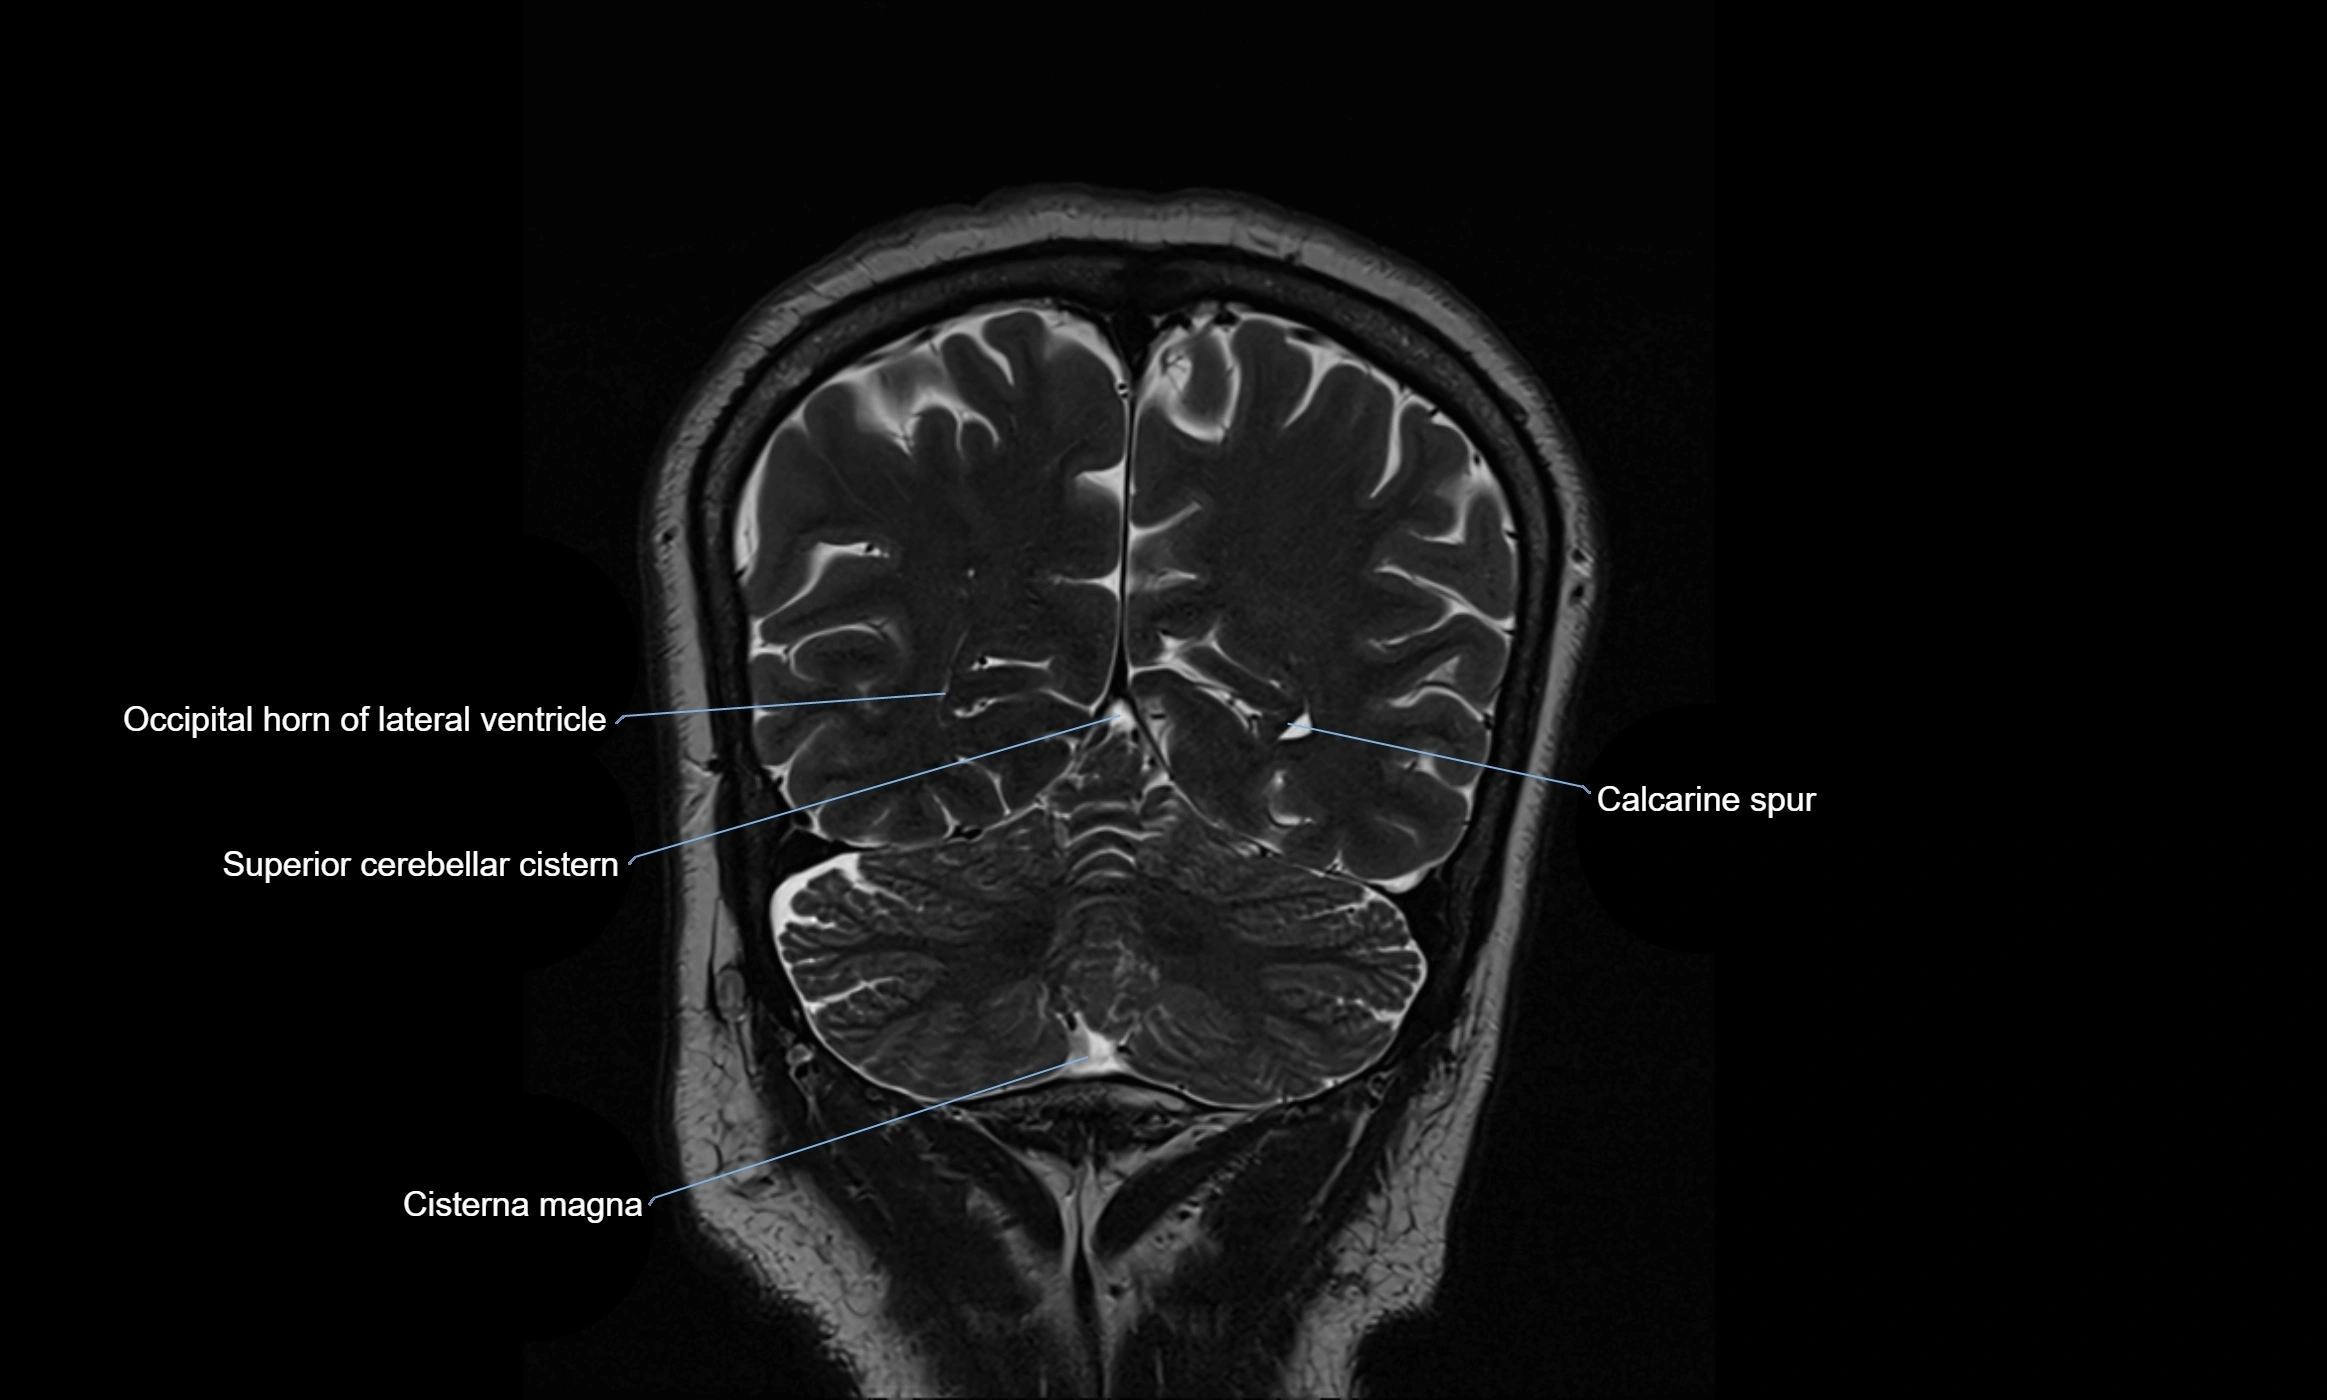

MRI images

image